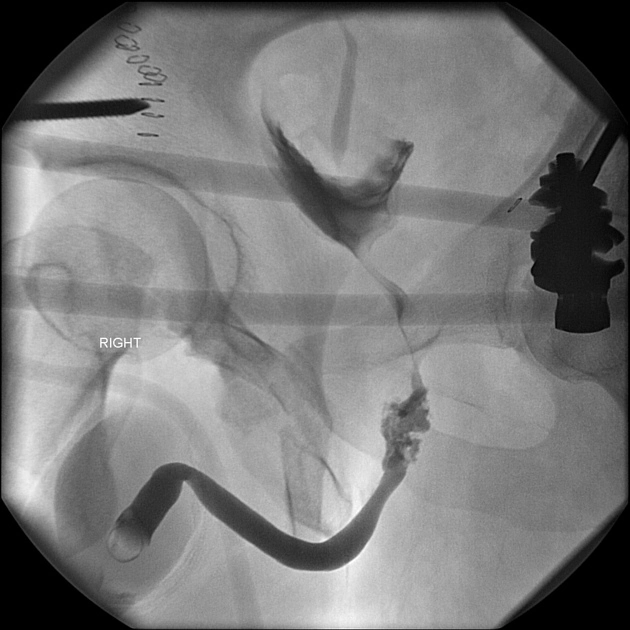

Chấn thương niệu đạo (Urethral injury)

Gãy dương vật (Penile fracture)

Bệnh Peyronie (xơ chai dương vật)